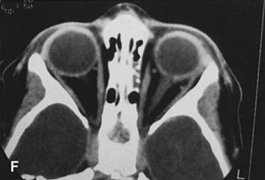

Fig. 14. A,B. Large intraorbital lymphangioma causing proptosis and optic nerve compression

the procedure. E. Postoperative appearance of the patient. F. The postoperative CT scan shows complete removal of the lymphangioma. This

large and diffuse lesion would have been difficult to remove with